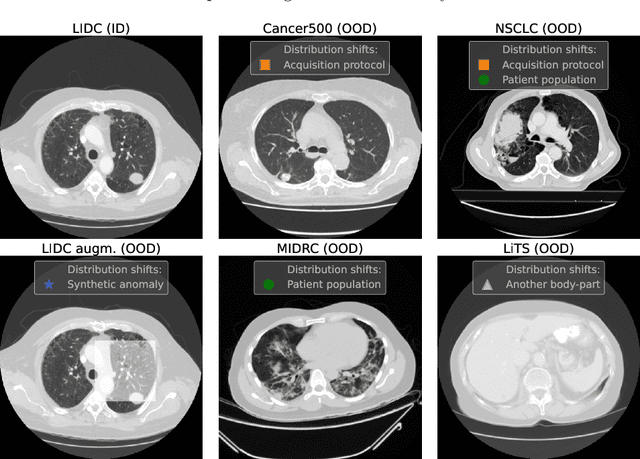

Abstract:Deep Learning models perform unreliably when the data comes from a distribution different from the training one. In critical applications such as medical imaging, out-of-distribution (OOD) detection methods help to identify such data samples, preventing erroneous predictions. In this paper, we further investigate the OOD detection effectiveness when applied to 3D medical image segmentation. We design several OOD challenges representing clinically occurring cases and show that none of these methods achieve acceptable performance. Methods not dedicated to segmentation severely fail to perform in the designed setups; their best mean false positive rate at 95% true positive rate (FPR) is 0.59. Segmentation-dedicated ones still achieve suboptimal performance, with the best mean FPR of 0.31 (lower is better). To indicate this suboptimality, we develop a simple method called Intensity Histogram Features (IHF), which performs comparable or better in the same challenges, with a mean FPR of 0.25. Our findings highlight the limitations of the existing OOD detection methods on 3D medical images and present a promising avenue for improving them. To facilitate research in this area, we release the designed challenges as a publicly available benchmark and formulate practical criteria to test the OOD detection generalization beyond the suggested benchmark. We also propose IHF as a solid baseline to contest the emerging methods.

Abstract:Deep Learning (DL) models tend to perform poorly when the data comes from a distribution different from the training one. In critical applications such as medical imaging, out-of-distribution (OOD) detection helps to identify such data samples, increasing the model's reliability. Recent works have developed DL-based OOD detection that achieves promising results on 2D medical images. However, scaling most of these approaches on 3D images is computationally intractable. Furthermore, the current 3D solutions struggle to achieve acceptable results in detecting even synthetic OOD samples. Such limited performance might indicate that DL often inefficiently embeds large volumetric images. We argue that using the intensity histogram of the original CT or MRI scan as embedding is descriptive enough to run OOD detection. Therefore, we propose a histogram-based method that requires no DL and achieves almost perfect results in this domain. Our proposal is supported two-fold. We evaluate the performance on the publicly available datasets, where our method scores 1.0 AUROC in most setups. And we score second in the Medical Out-of-Distribution challenge without fine-tuning and exploiting task-specific knowledge. Carefully discussing the limitations, we conclude that our method solves the sample-level OOD detection on 3D medical images in the current setting.